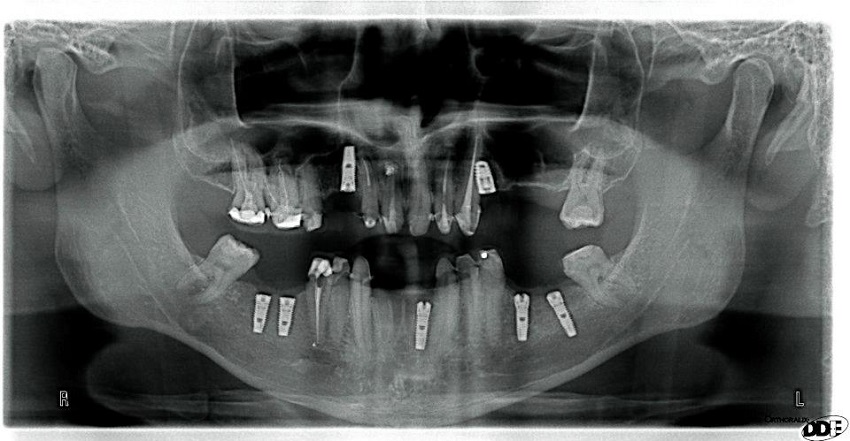

Implantologija je zahvat kojim se titanski vijci ugrađuju u kost gornje ili donje čeljusti tako da oni imitiraju korijen zuba i djeluju kao nosači za zubne krunice, mostove i proteze.

Zubni implantanti idealan su izbor za pacijente kod kojih je potrebno nadomjestiti jedan ili više zubi.

- 3D dijagnostika - digitalni ortopan

- Orthophos SL 3D